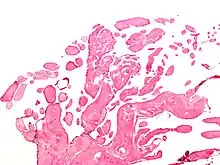

| Micrograph of a papillary fibroelastoma, a benign tumor of heart valves. H&E stain. | |

- Papillary Fibroelastoma

A subset of the primary tumors of the heart are tumors that are found on the valves of the heart. Tumors that affect the valves of the heart are found in an equal distribution among the four heart valves.[2] The vast majority of these are papillary fibroelastomas. Primary tumors of the valves of the heart are more likely to occur in males. While most primary tumors of the valves of the heart are not malignant, they are more likely to have symptoms related to the valve, including neurologic symptoms and (in a few cases) sudden cardiac death.